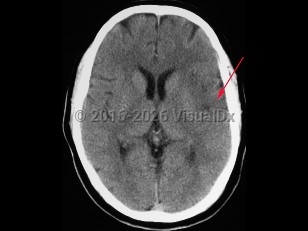

- Intracerebral hemorrhage – Bleeding directly into the brain parenchyma secondary to hypertension, trauma, bleeding disorders, aneurysm rupture, illicit drug use, or vascular malformations. Patients typically present with the gradual onset of symptoms over hours to days with headache, nausea, vomiting, and altered levels of consciousness. If the source of the hemorrhage is from the low-pressure side of the circulation, then the onset of symptoms is more likely to be gradual than if the source is from the high-pressure, arterial side, where symptoms can be quite abrupt in onset. Patients can also present with seizure.

Risk factors for hemorrhagic stroke include hypertension, age, use of anticoagulants, arteriovenous malformations, and use of illicit drugs like cocaine.